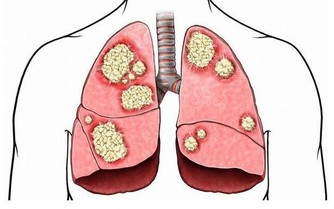

除了體溫升高,發燒還往往伴隨感覺冷、皮膚發紅發燙、頭痛、身體痛、疲勞虛弱、食慾不振、心率加快、脫水等症狀。